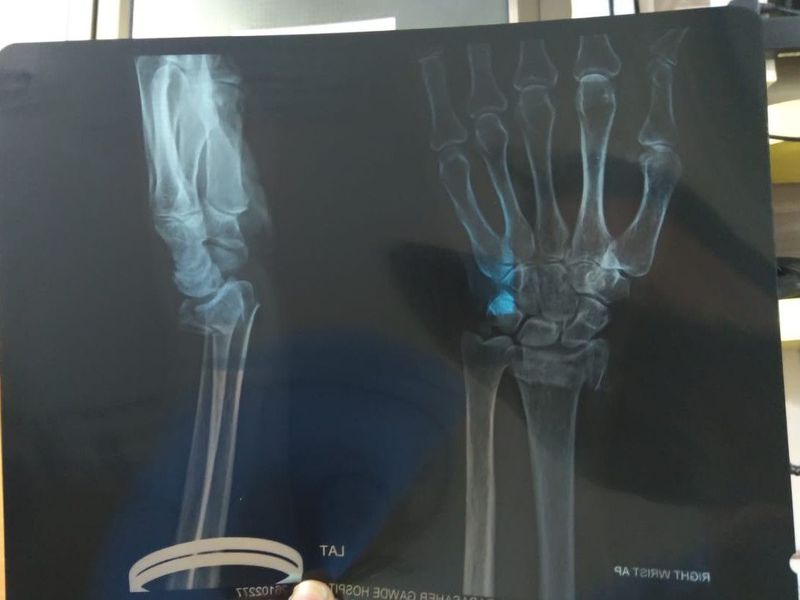

Radiology

Fracture

Management

Closed reposition and K wire stabilisation.